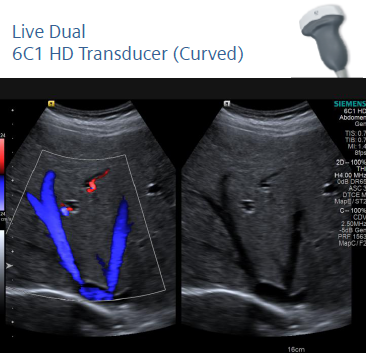

SIEMENS S2000 z zaawansowaną elastografią

Ultrasonograf uruchamia się bez żadnych problemów i wyświetlanych błędów. Klawiatura, trackball, przyciski wzmocnienia w bardzo dobrym stanie technicznym. Podnoszenie konsoli góra/dół, lewo/prawo działa prawidłowo. Wszystkie tryby obrazowania działają poprawnie. Ogólnie system i głowice w bardzo dobry stanie wizualnym i technicznym.